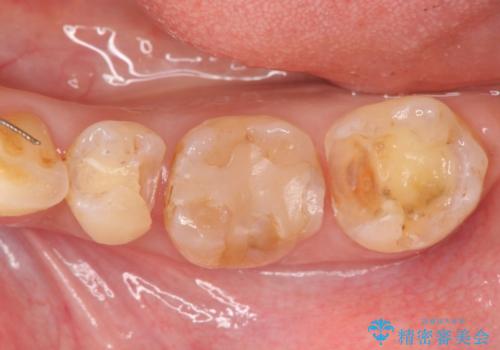

銀歯の下で虫歯の再発 拡大鏡下で行う虫歯の精密治療

- 他院で銀歯の下部に再発した虫歯の存在を指摘され、精密な治療を求めて来院されました。

銀歯下に虫歯が再発すると神経に近くなり、根管治療を必要とする可能性が高まってしまいます。

健全な歯を削らないように拡大鏡下で丁寧に虫歯を除去することで神経を温存し精密なセラミック治療を行うことができました。